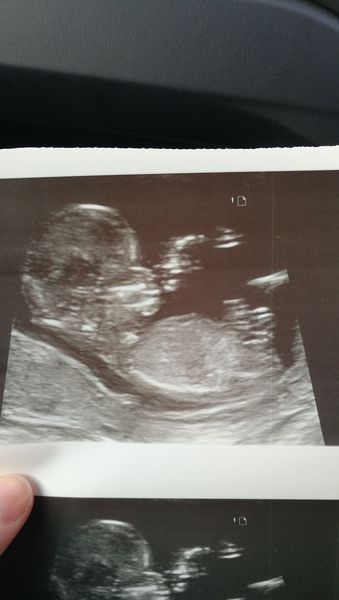

avacadooo · 01/02/2019 11:52

Just had my scan, everything is good! New due date of the 11th!

Also my baby is apparently 90% leg 😂😂

@avacadooo looking very relaxed in there!!

@avacadooo such a great a scan. Baby is very relaxed putting their feet up!! 😂

@avacadooo that scan is great looks like you may have trouble evicting that one when the time comes they've really made themselves at home already Grin

Wow what a great scan pic xx

Aww lovely scan photo @avacadooo xxx

@avacadooo oh my god what a fab scan pic! So chilled out 😂 delighted scans went well today for everyone ❤